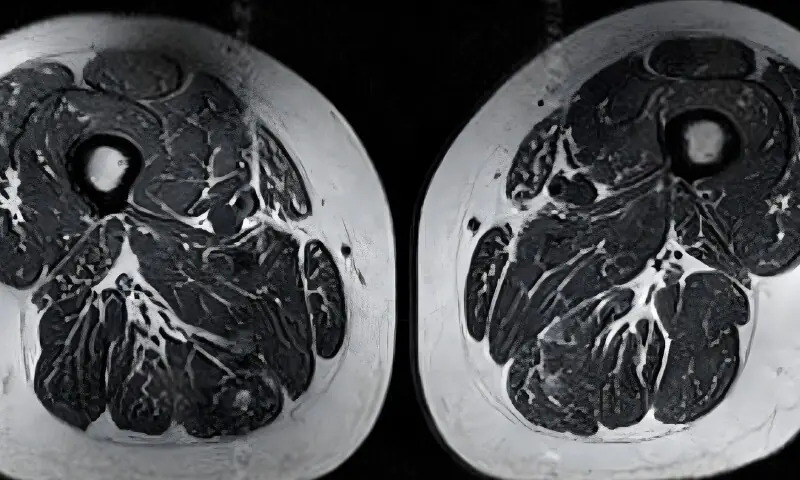

ریڈیالوجی جرنل میں شائع ہونے والی نئی اسٹڈی کے مطابق جو لوگ اپنی روزمرہ خوراک کا زیادہ تر حصہ ان غذاؤں پر مشتمل رکھتے ہیں، ان کی رانوں کے پٹھوں میں چربی کی کئی تہیں بن جاتی ہیں۔

تحقیق میں ایک 62 سالہ خاتون کے ایم آر آئی اسکین کا حوالہ دیا گیا ہے جس کی 87 فیصد خوراک مصنوعی مشروبات، چاکلیٹ اور الٹرا پروسیسڈ کھانوں پر مشتمل تھی۔

اسکین سے معلوم ہوا کہ ان کے پٹھوں کے ریشوں کے درمیان چربی اس قدر سرایت کر چکی تھی کہ پٹھے اپنی طاقت کھو چکے تھے۔

سی این این میں شائع ہونے والی ایک رپورٹ کے مطابق ماہرین کا کہنا ہے کہ پٹھوں میں چربی کا یہ پھیلاؤ ایک عضو تک محدود نہیں رہتا بلکہ پورے جسم کے پٹھے متاثر ہو سکتے ہیں، جس سے جسمانی کمزوری اور مستقبل میں بیماریوں کا خطرہ بڑھ جاتا ہے۔ یہ کیفیت خاص طور پر موٹاپے کے شکار افراد میں زیادہ سنگین ہو سکتی ہے۔